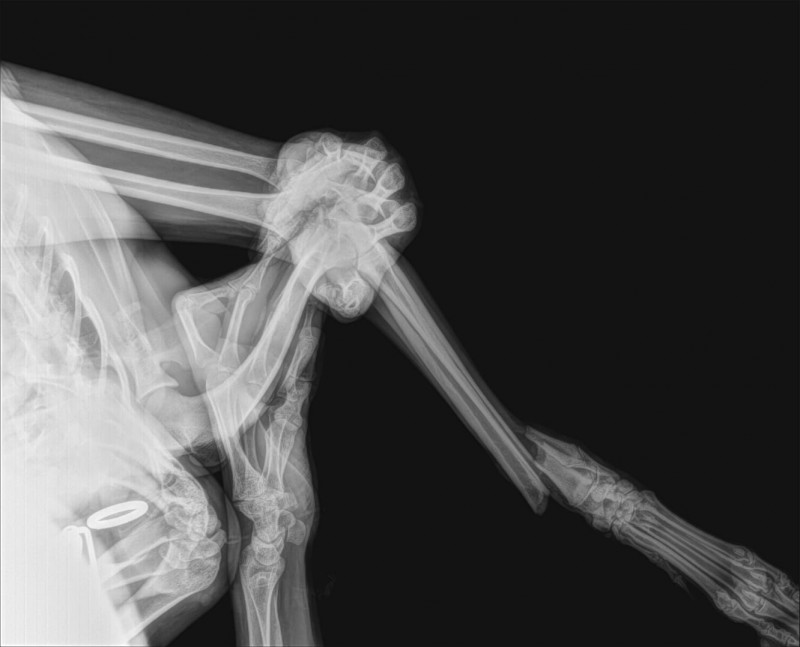

DES news de notre MERLIN suite RDV du 06.01.2025 :

Après un contrôle radios, les plaques ainsi que les vis des deux pattes côté gauche ont été enlevés.

Nous en avons profité pour faire faire la castration.

La patte arrière gauche : cela suit son cours et tout va très bien.

Au niveau de la patte avant gauche : tout le matériel a été enlevé, l'orthopédiste a fait un carottage pour biopsie osseuse au niveau de l’infection dans l’os où était la plaque (tout le matériel a aussi été envoyé au labo pour analyse).

Selon le résultat, il sera peut être envisagé de remettre une petite plaque flexible. Cela dépendra de l’évolution de l’infection osseuse.

Encore deux semaines pendant lesquelles notre galguito ne doit pas bouger car la patte avant est fragilisée.

Un contrôle radio est prévu le 22.01.2025.